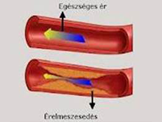

• Érelmeszesedés valóban elkerülhető, megakadályozható, visszafordítható?

• Az érelmeszesedés megelőzése, korlátozása, visszafordíthatósága

Az érelmeszesedés nem jár együtt a korral – már huszonéveseknél is kialakulhat. Az érfalakban keletkező lerakódások és az érfalak merevvé válása nem időskori jelenség. Hol vannak az érelmeszesedés tipikus helyei? Az érelmeszesedés kialakulása.

Homocisztein káros hatása az érelmeszesedésre. Az érfal (endothelium) sérülésének oka. Az érfal (endothelium) sérülésének oka. Az egészséges endothel működésében központi szerepet játszik a nitrogén-monoxid (NO). Érelmeszesedés megelőzése, csökkentési lehetősége, kezelése. Rezveratrol, fokhagyma, Golden Yacca Plus, K2 vitamin kedvező hatása. Sztatin gyógyszer hatása az érelmeszesedésre.

Szintetikus gyógyszerek hatása. Érelmeszesedés megelőzése, csökkentési lehetősége, kezelése